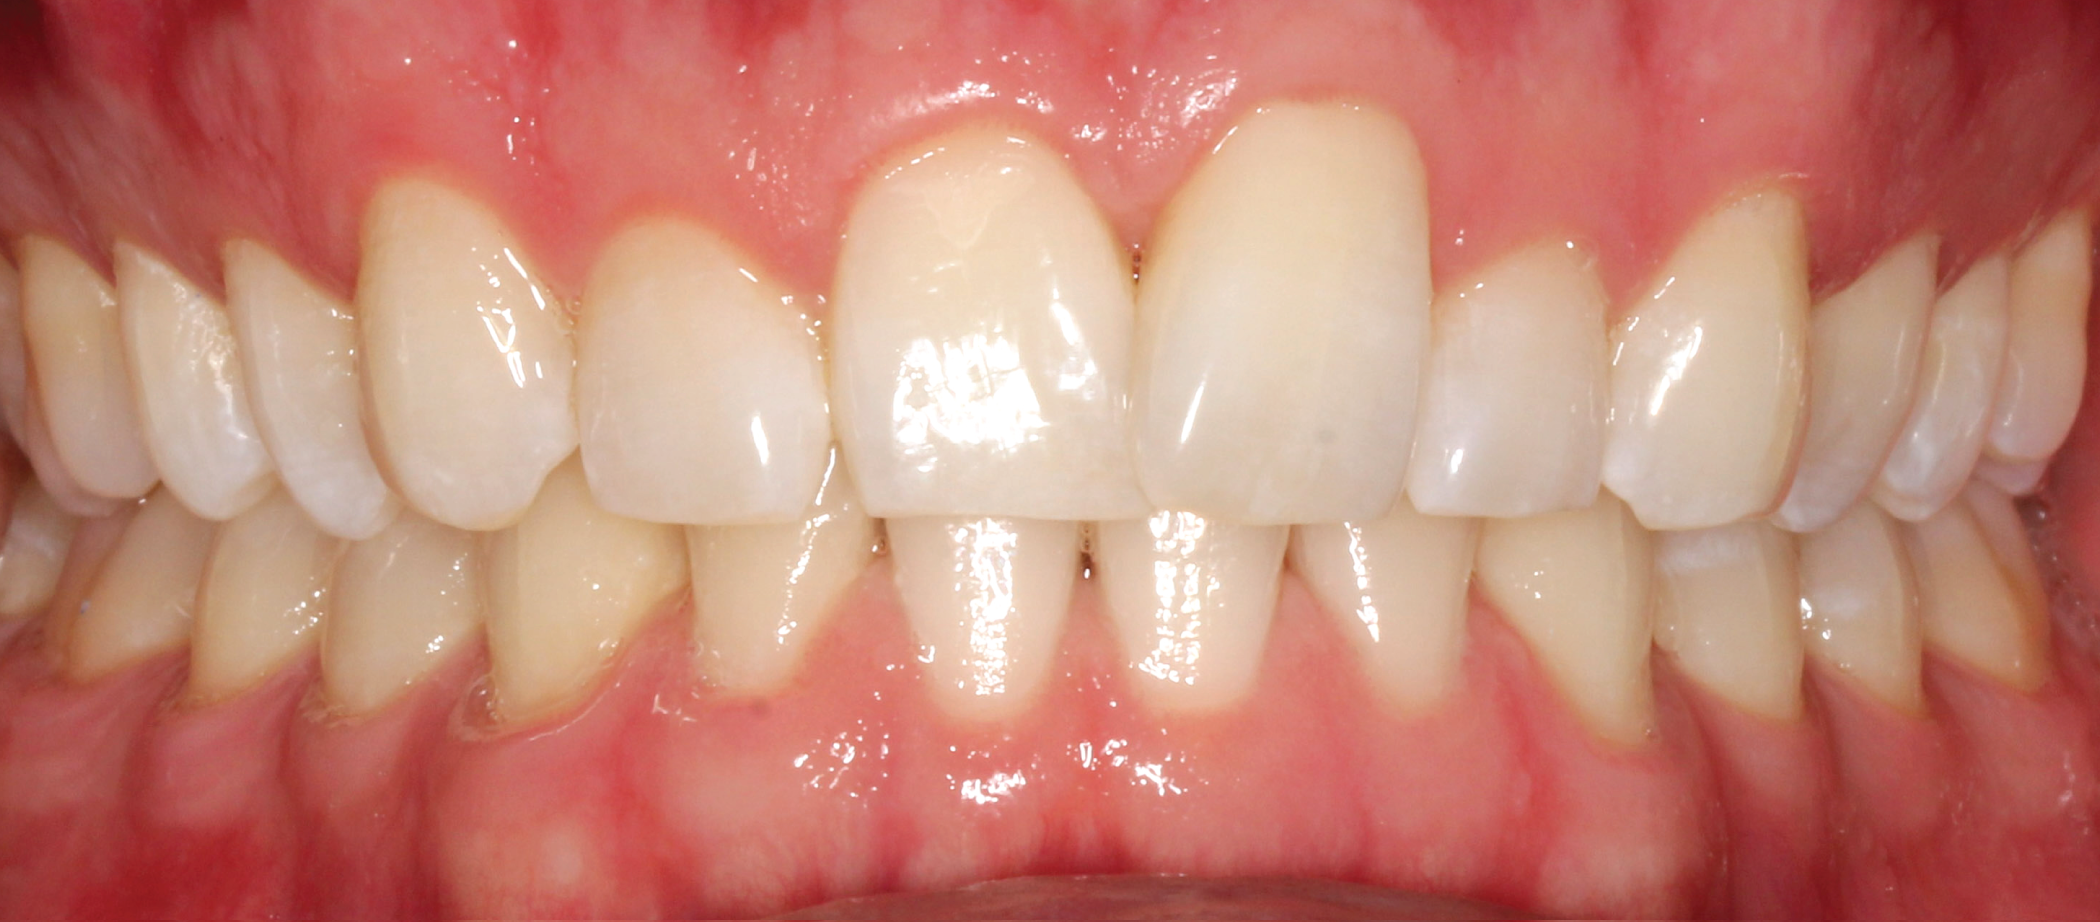

A 32-year-old male patient presented with a chief complaint of rotated tooth 9 and uneven anterior gingival heights. The patient was not interested in traditional orthodontic brackets and wires and decided on clear aligner therapy due to its esthetic and hygienic advantagesUpon reviewing the process with the patient, the decision was made to initiate ClearCorrect clear aligner therapy. The patient consented and the appropriate impressions and photos were submitted to ClearCorrect for a treatment setup.

The treatment goals for clear aligner therapy were focused on rotating tooth 9, extruding tooth 9 and subsequent enameloplasty to even out the maxillary anterior teeth. The patient also had mild Class II molar and canine relationships with crowding and spacing discrepancies in the anterior teeth. The goal with the extrusion of tooth 9 was to move the adjacent bone and soft tissue coronal with the tooth movement. Additional space was needed for the maxillary teeth to accommodate the rotation of tooth 9 into the correct position. Lastly, extra spacing between the lower teeth was to be treated along with the mild Class II malocclusion (Figs. 1-8).

Fig 3: Pre-op (front view) Fig. 4: Pre-op (front view, open)